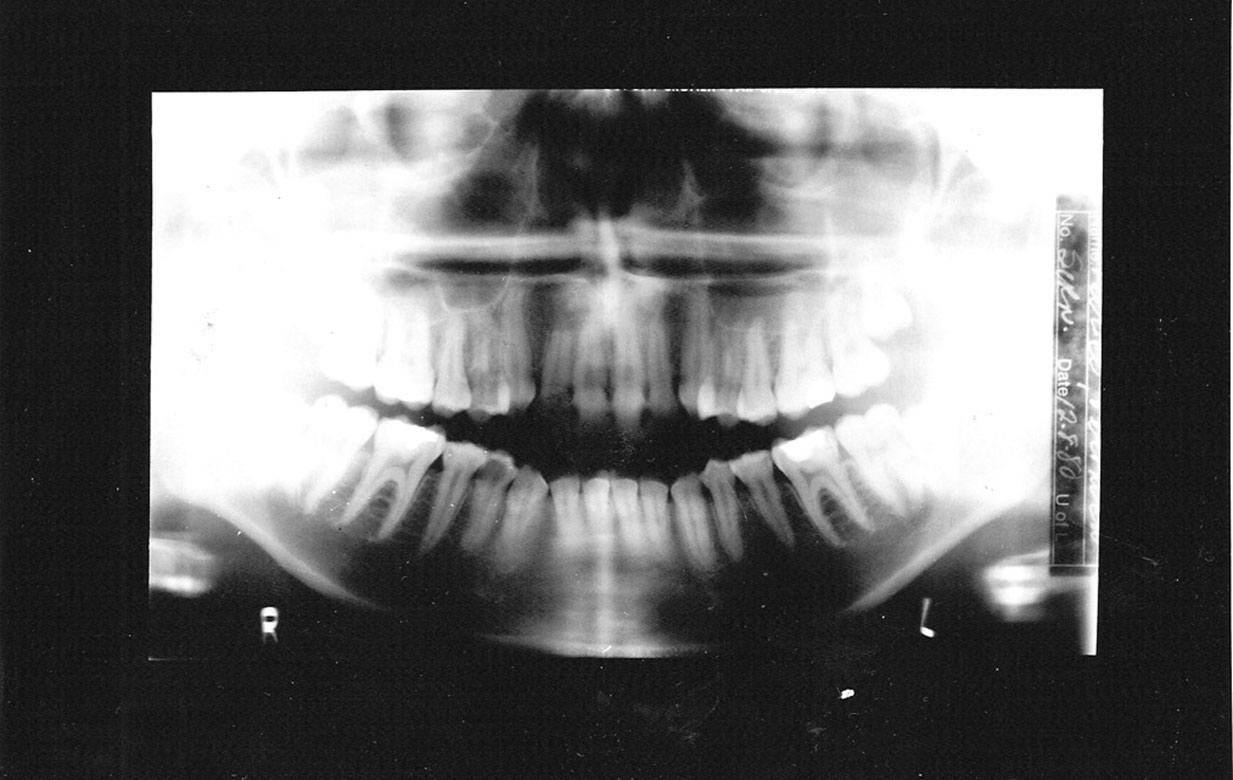

Figure 23. Panoramic films - top-normal; bottom - showing movement.

Figure 23

Motion

Vertical, horizontal or compound patient movements and slippage or vibration of the tubehead or film holder can produce a range of artifacts on panoramic films. With conventional films, motion produces generalized unsharpness; with panoramic films, however, motion unsharpness only affects the portion of the film that was being exposed at the time motion occurred. Therefore, depending on the extent and duration of movement, only a small, discreet portion of the exposure may be blurred while the rest of the film is within acceptable limits. Short-duration movement may be difficult to detect because the resulting artifact can look suspiciously like a pathological condition.

The top radiograph in Figure 23 is a normal panograph. The bottom panograph is one that was affected by short-duration movement. Notice how the patient’s left mandible appears to be notched along the upper margin. The notch could easily be interpreted as calcification at an old fracture site when, in reality, it is a movement artifact. Remember, when viewing radiographs, the patient’s left is on the viewer’s right.